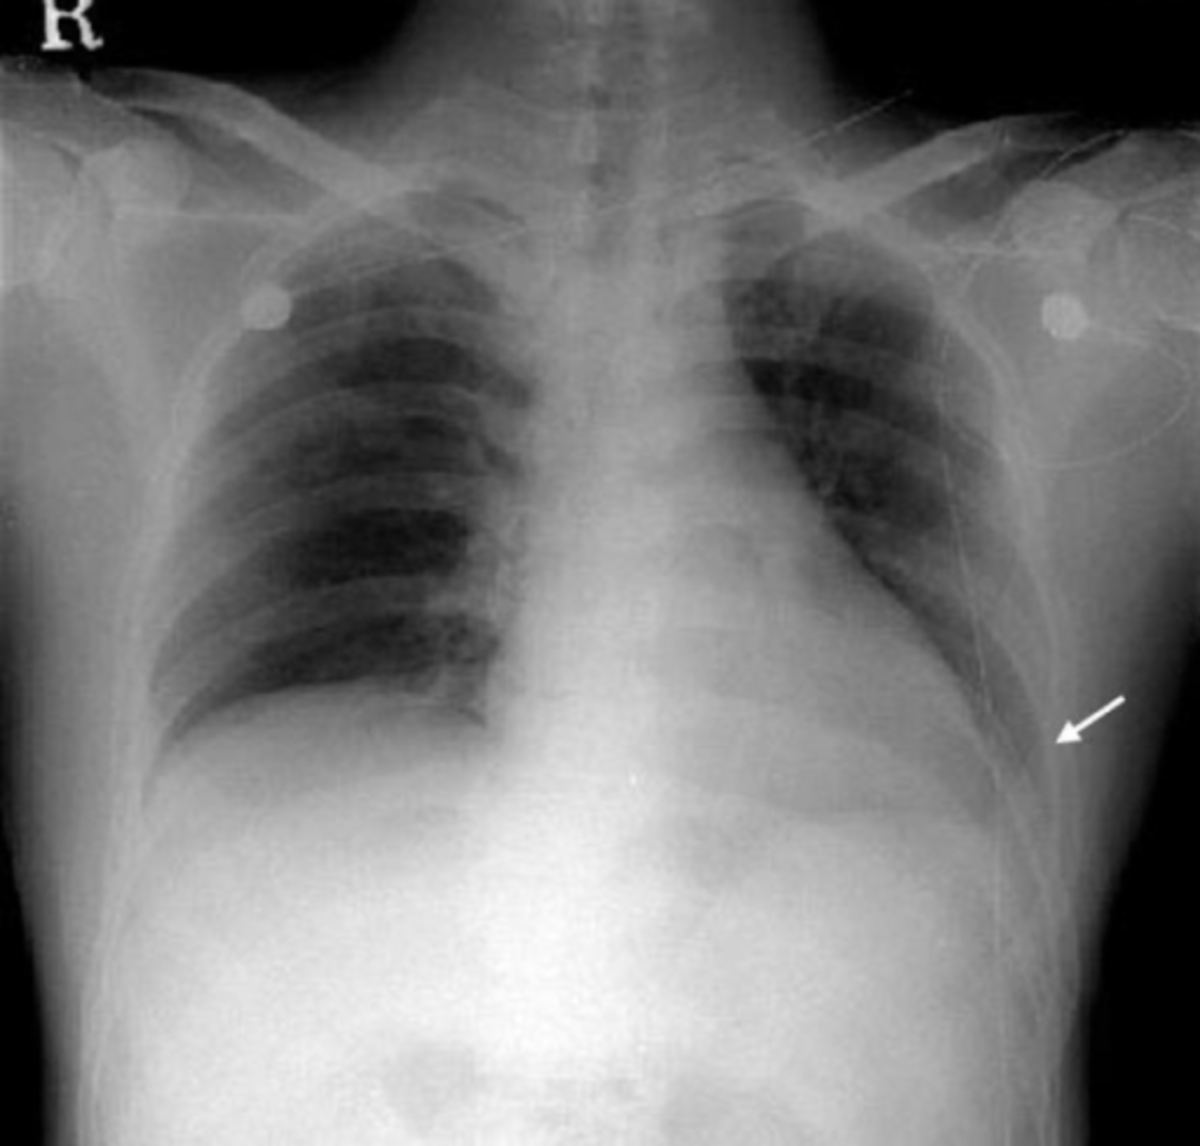

The chest Xray showing fluid accumulation of the right pleural cavity Chest X Ray For Fluid In Lungs There can also be fluid in other parts of the chest like in the mediastinum, along the. Tests that can help diagnose pulmonary edema or determine the reason for fluid in the lungs include: Pulmonary edema is the abnormal buildup of “fluid in the lungs.” fluid buildup in your lungs can lead to shortness of breath, coughing up. Pleural effusion,. Chest X Ray For Fluid In Lungs.

A chest xray film of a patient with massive pleural effusion. Fluid in Chest X Ray For Fluid In Lungs Pulmonary edema is the abnormal buildup of “fluid in the lungs.” fluid buildup in your lungs can lead to shortness of breath, coughing up. The chest radiograph remains the most practical and useful method of radiologically assessing and quantifying pulmonary edema 3,4. There can also be fluid in other parts of the chest like in the mediastinum, along the. There. Chest X Ray For Fluid In Lungs.